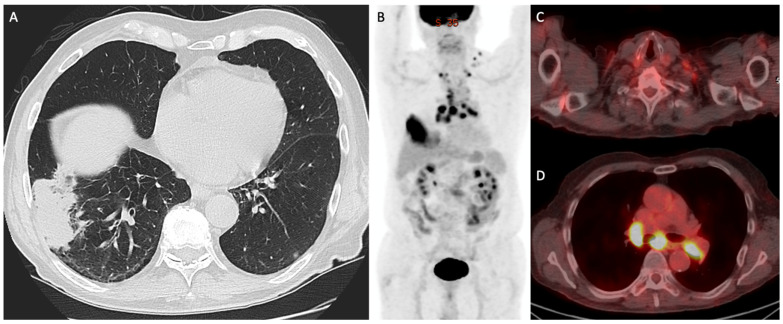

Figure 3.

Demonstrates a 68-year-old man with biopsy-proven right lung adenocarcinoma (Stage: T3N3M0). (A) Axial CT showing a mass in the lateral right lower lobe, abutting adjacent pleura, with biopsy demonstrating adenocarcinoma. (B) 18F-FDG-PET/CT maximum-intensity projection and (C,D) fused images showing multiple enlarged, avid ipsilateral and contralateral mediastinal and supraclavicular lymph nodes, suspicious for metastases, with the left supraclavicular node subsequently biopsied confirming malignancy.